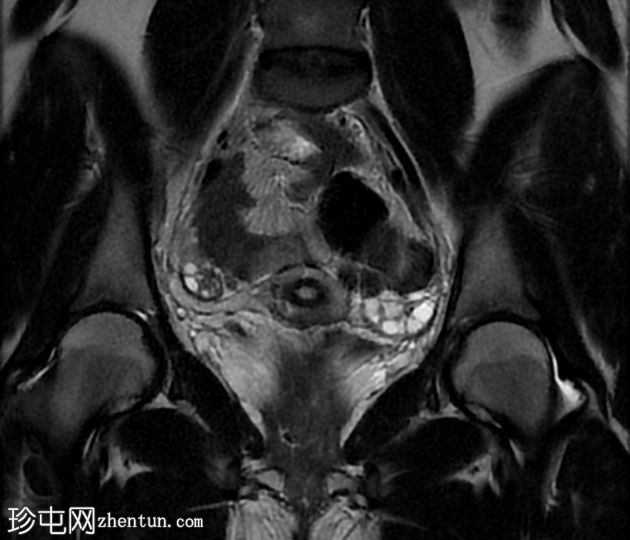

冠状位

STIR序列

子宫前倾位,分区解剖结构正常。矢状位序列可见子宫前壁肌层局灶性边界不清的低信号病灶,但在后续序列中未见明显,符合短暂的生理性子宫肌层收缩表现。

双侧卵巢大小及卵泡活动均正常。未见囊性或实性肿块。

该病例的盆腔器官MRI表现与患者年龄(14岁)相符,子宫位置正常,分区解剖结构正常,双侧卵巢大小及卵泡活动均正常,未见囊性或实性肿块。

此外,MRI还意外发现子宫肌层局灶性病变,T2信号低,易被误诊为子宫肌瘤。然而,该病变在后续序列中消失,符合短暂的生理性子宫肌层收缩所致。